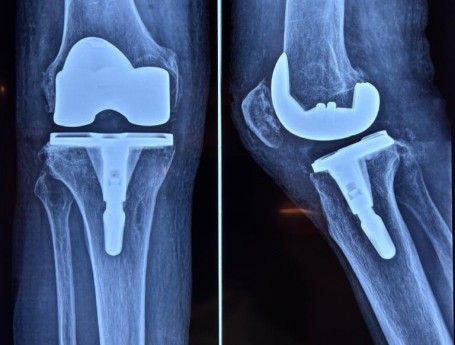

Total Knee Arthroplasty on a severe Genu Valgum

• Total Knee Arthroplasty on a severe Genu Valgum